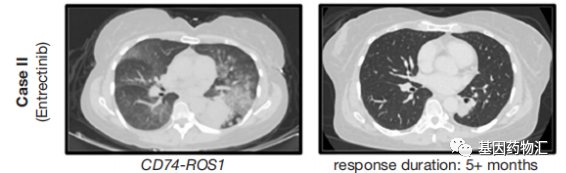

另一位患者,60岁女性,无吸烟史,确诊时为右下叶肺腺癌,且颅脑成像提示了8个颅内病灶。二代测序提示了CD74-ROS1(C6:R33)融合突变,同样在第一代ROS1抑制剂的适应症范围内。但由于患者存在脑转移,因此一线治疗并没有选择克唑替尼,而是选择了入脑活性更强的恩曲替尼,每天600 mg剂量。

患者经历了一些不良事件,例如头晕、步态不稳和腹泻,因此将恩曲替尼的剂量减少至400 mg,疗效整体稳定,病灶以及颅内病灶持续缩小。